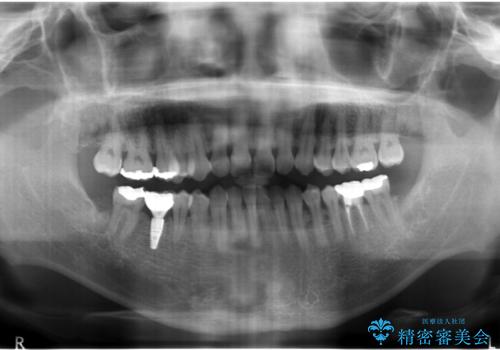

- 右下の奥歯にインプラントを入れたいと来院。

抜歯から時間が経っており、骨が十分あったためすぐにインプラントを入れることが可能でした。骨も補う必要がありませんでした。

手術が怖いとのことで、外科手術時には静脈麻酔を行い、眠っている間に手術が終わるようにしました。

- 52万円 内訳:ストローマンインプラント(1本)42万円(仮歯、ジルコニアクラウン、カスタムアバットメント含む) 静脈麻酔 5万円x2回費用は治療当時の料金となります

インプラント手術時に同時に親知らずの抜歯も行い、腫れや痛みなどを1度で終わらせるようにしました。